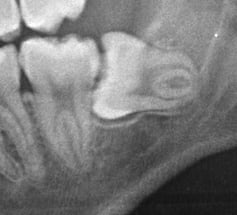

埋状歯(顎の骨または歯肉の下に埋もれて出てこない歯。)

水平埋状歯(横向きに埋もれて出てこない歯。下顎の親知らずでよく見かけます。)